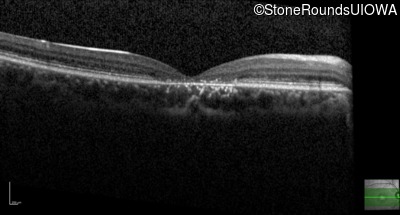

Age at visit: 21 years

Age at visit: 23 years

Age at visit: 25 years

The clinical features favoring the diagnosis of ABCA4-associated autosomal recessive Stargardt disease include: loss of acuity in the second decade, reduction in color discrimination and foveal photoreceptor loss on OCT.